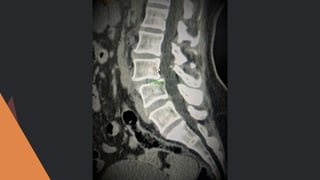

Preoperative and post operative CT SCAN is

taken

Facet angle, disc height and lateral listhesis is

noted both preoperative and postoperative

RADIOLOGICAL EVALUATION

Preoperative and postoperative CT SCAN is taken Facet angle, disc height and lateral listhesis is noted both preoperative and postoperative RADIOLOGICAL EVALUATION